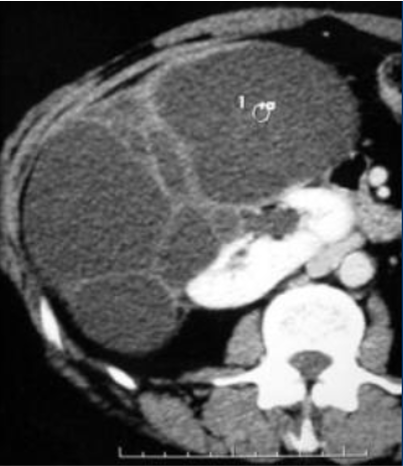

is this mass enhancing?

yes!

new finding. Management?

excise it